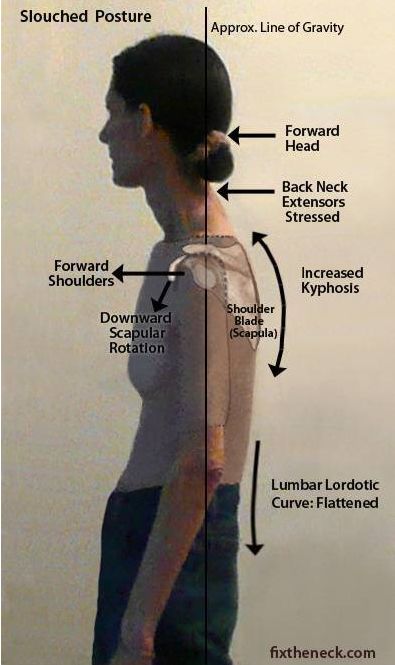

· 圆肩探头:也就是上交叉综合征,从侧面观察能看到头部前移,颈椎承受负荷增加,同时肩膀向内向前收。

· 驼背:由于胸椎过度向后 弯曲 导致,从侧面观察时可以看到上背部向后拱起。驼背和圆肩有时容易搞混,要明确是胸椎向后拱还是肩膀向内收。

生活 、工作中的所有习惯,都是形成各种各样不同体态的非常重要的原因。长期伏案工作的人,容易导致含胸驼背; 长期看电脑的人,容易导致头前探; 长期背重物会加剧含胸驼背探头,甚至造成足弓塌陷; 长期工作穿高跟鞋易导致 盆骨 前倾、膝超伸。这些长期的习惯导致了身体的前后肌肉张力失去平衡,时间久一点,肌肉软 组织 就会拉着骨关节去到不该去的位置,最终使骨关节的排列出现异常,导致我们形成了形态各异的身体姿势。

保持身体内部 系统 的最佳化活动

当长时间驼背,脊柱在屈曲位的时候会压迫到我们的 呼吸 系统,造成头晕胸闷的情况; 当骨盆位置位移时,会导致 肠道 系统也发生相应位置的改变,从而造成 便秘 等系列问题; 当肩胛骨长期处于耸肩的情况,会压迫到我们的颈部后侧的 神经,和前侧的臂丛神经,造成手麻头痛等情况。